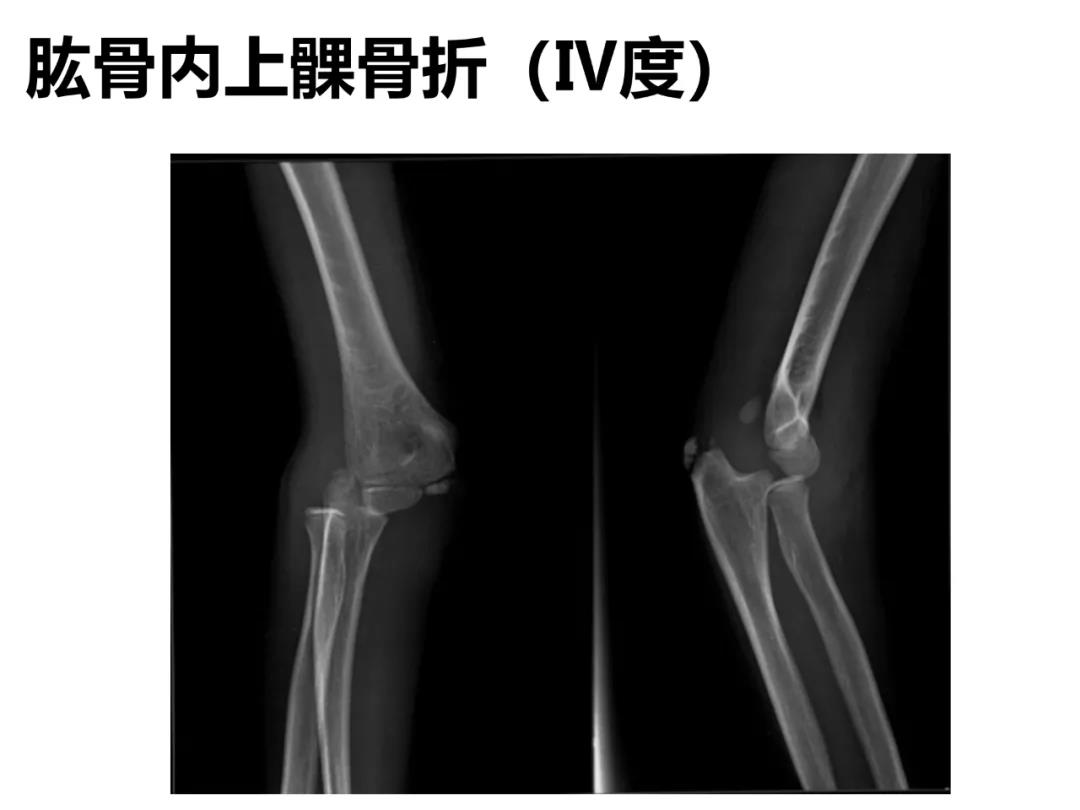

小儿骨科X线片汇总,临床读片宝典!